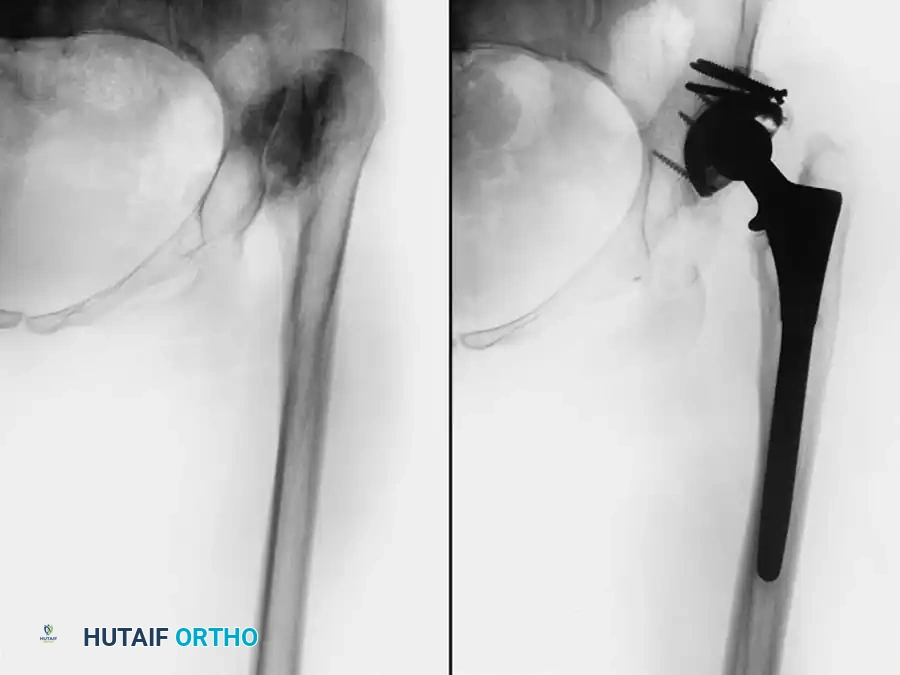

Fig. 7-75 Reconstruction for protrusio acetabuli deformity. A, Diagrammatic representation of medial wall grafting and lateralized cup placement.

Fig. 7-75 Reconstruction for protrusio acetabuli deformity. B, After total hip arthroplasty. Hip center was restored to more lateral and inferior position. Large acetabular component allowed rim fixation without need for screws, and medial deficits were grafted with cancellous autograft from femoral head with excellent incorporation.